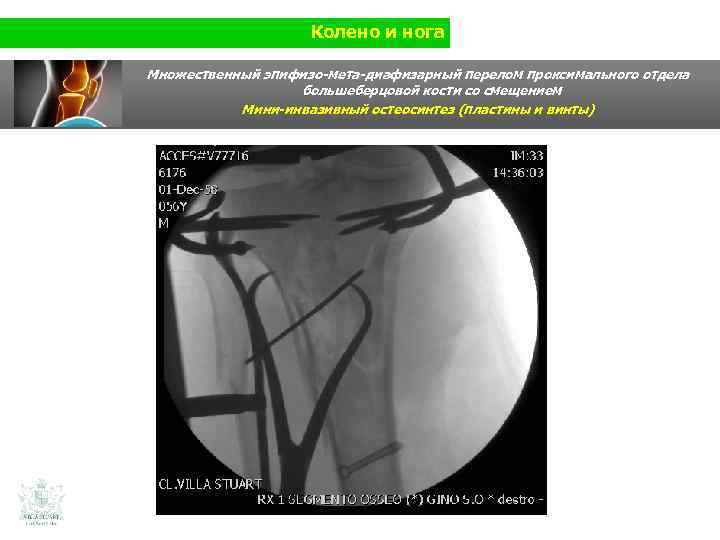

Колено и нога Множественный эпифизо-мета-диафизарный перелом проксимального отдела большеберцовой кости со смещением (Shatzer 6) Мини-инвазивный остеосинтез ( пластины и винты)

Колено и нога Множественный эпифизо-мета-диафизарный перелом проксимального отдела большеберцовой кости со смещением Мини-инвазивный остеосинтез ( пластины и винты)